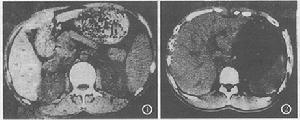

膽道華支睪吸蟲病CT圖華支睪吸蟲病的流行必須具備3個條件:①有適於病原體寄生的終宿主;②糞便污染水源,同時有一定數量的中間宿主-淡水螺、魚、蝦的存在;③當地居民有不良的飲食習慣,進食含囊蚴的淡水魚蝦,如食“魚生”(生魚片)、“生滾粥”(生魚片加熱煮成的粥)、進食燒烤的小魚,追求進食鮮、活、嫩滑的生食等。

膽道華支睪吸蟲病病理圖在流行區,由於人們普遍對膽道華支睪吸蟲病有所認識,根據臨床表現等很容易確診但在非流行區易導致誤診依據流行病學資料、臨床症狀和體徵、結合實驗室檢查及影像學檢查可明確診斷。